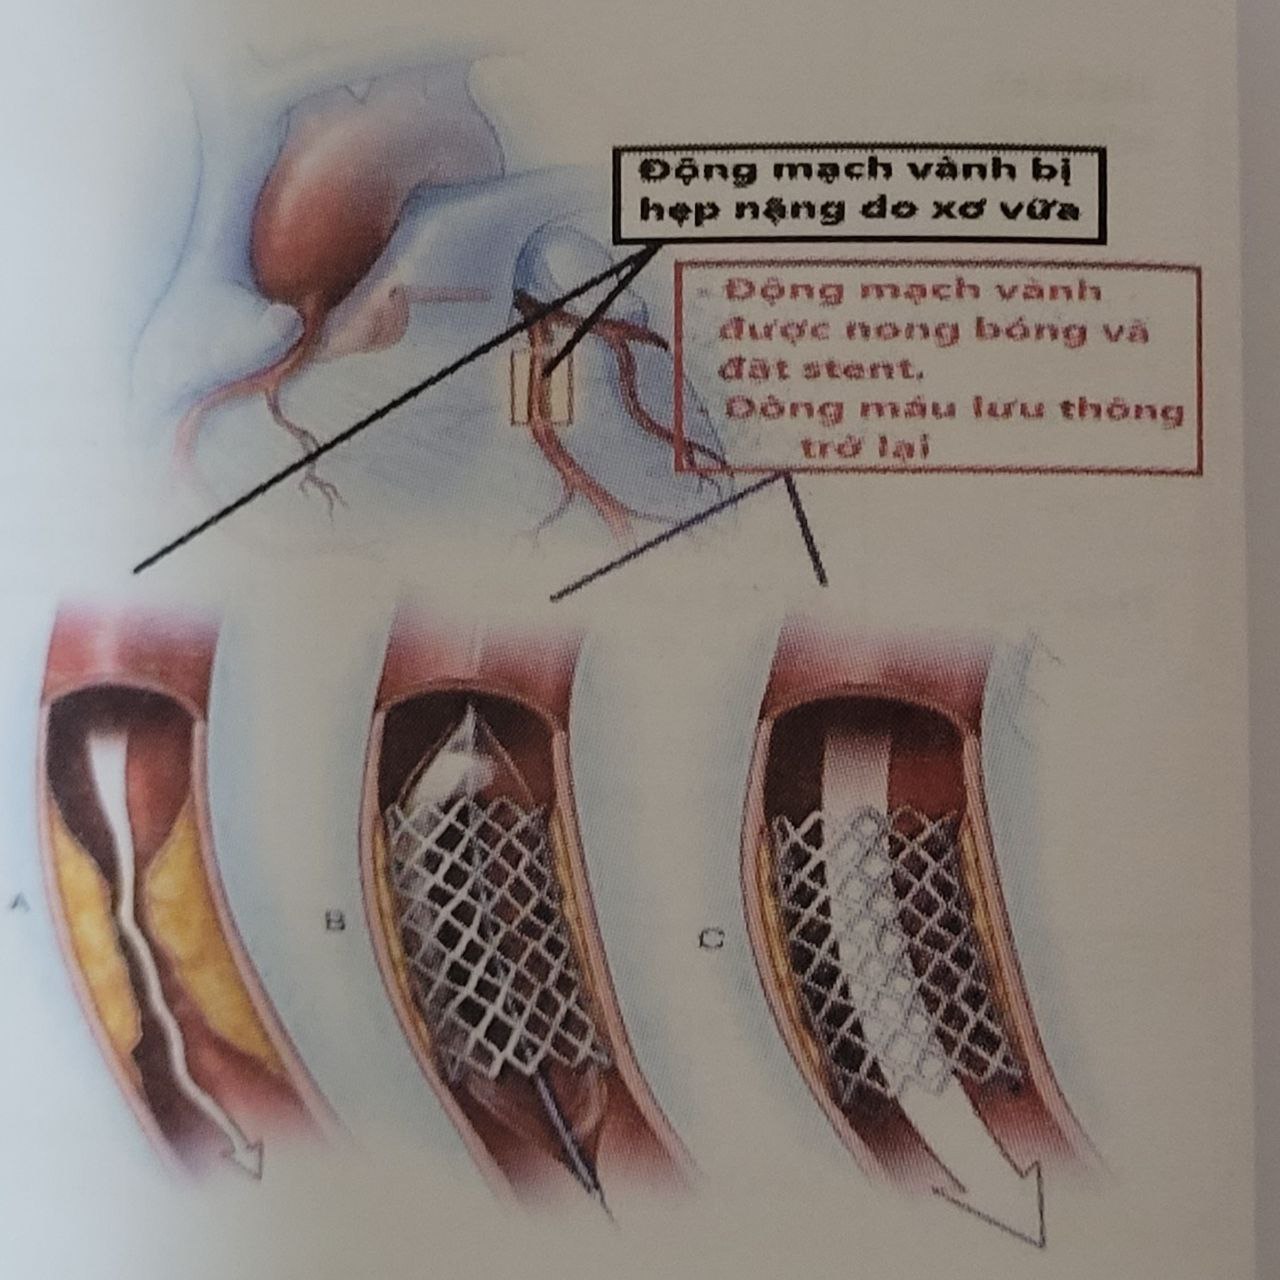

6.2. Điều trị thủ thuật – phẫu thuật tái thông động mạch vành

Phẫu thuật động mạch vành

Phẫu thuật động mạch vành

Các bác sĩ đang làm thủ thuật trong phòng DSA – đặt stent động mạch vành

Các bác sĩ đang làm thủ thuật trong phòng DSA – đặt stent động mạch vành

– Chụp nong đặt stent động mạch vành qua da bằng máy DSA: nếu bệnh động mạch vành điều trị bằng thuốc không hiệu quả, tiến triển xấu hơn, những biện pháp chuyên sâu khác sẽ được cân nhắc thực hiện như chụp và có thể can thiệp mạch vành bằng phương pháp mạch máu số hóa xóa nền DSA. Khi động mạch vành hẹp nặng do xơ vữa sẽ cần phải xem xét đặt stent để khôi phục dòng máu xuôi cơ tim.